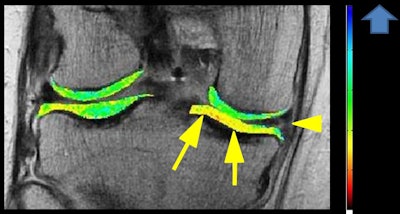

For quantitative and qualitative analyses using MRI, Roemer finds 3D morphometry particularly valuable.

"This is based on tissue segmentation and is being widely used for cartilage quantification," he said. "The cartilage tissue is well contrasted between the intra-articular fluid and the subchondral bone. Regions of interests are drawn around the cartilage, and multiple parameters can be extracted from those 3D segmentations, including cartilage volume, cartilage thickness, the amount of the denoted bone area beneath the cartilage, and so on."

Compositional MRI techniques, including T2 mapping or T2 relaxometry, can be used to look at the ultrastructure of tissue. Basically, the different analytical approaches are semiquantitative, quantitative, and qualitative compositional measures of tissue change, Roemer noted.